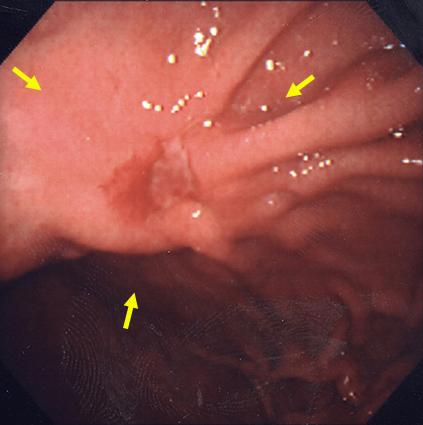

疾病(病理主体)的分类恶性上皮性肿瘤/腺癌

部位(按器官分)胃(部位)/体部

检查方法内窥镜

肿瘤的肉眼分类3型(溃疡浸润型)/

肿瘤最大直径30~34

肿瘤的深度mp